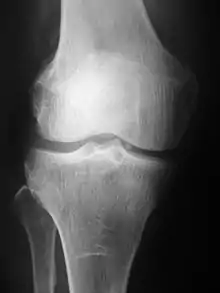

Radiographs (originally called roentgenographs, named after the discoverer of X-rays, Wilhelm Conrad Röntgen) are produced by transmitting X-rays through a patient. The X-rays are projected through the body onto a detector; an image is formed based on which rays pass through (and are detected) versus those that are absorbed or scattered in the patient (and thus are not detected). Röntgen discovered X-rays on November 8, 1895, and received the first Nobel Prize in Physics for his discovery in 1901.

Plain radiography was the only imaging modality available during the first 50 years of radiology. Due to its availability, speed, and lower costs compared to other modalities, radiography is often the first-line test of choice in radiologic diagnosis. Also despite the large amount of data in CT scans, MR scans and other digital-based imaging, there are many disease entities in which the classic diagnosis is obtained by plain radiographs. Examples include various types of arthritis and pneumonia, bone tumors (especially benign bone tumors), fractures, congenital skeletal anomalies, and certain kidney stones.